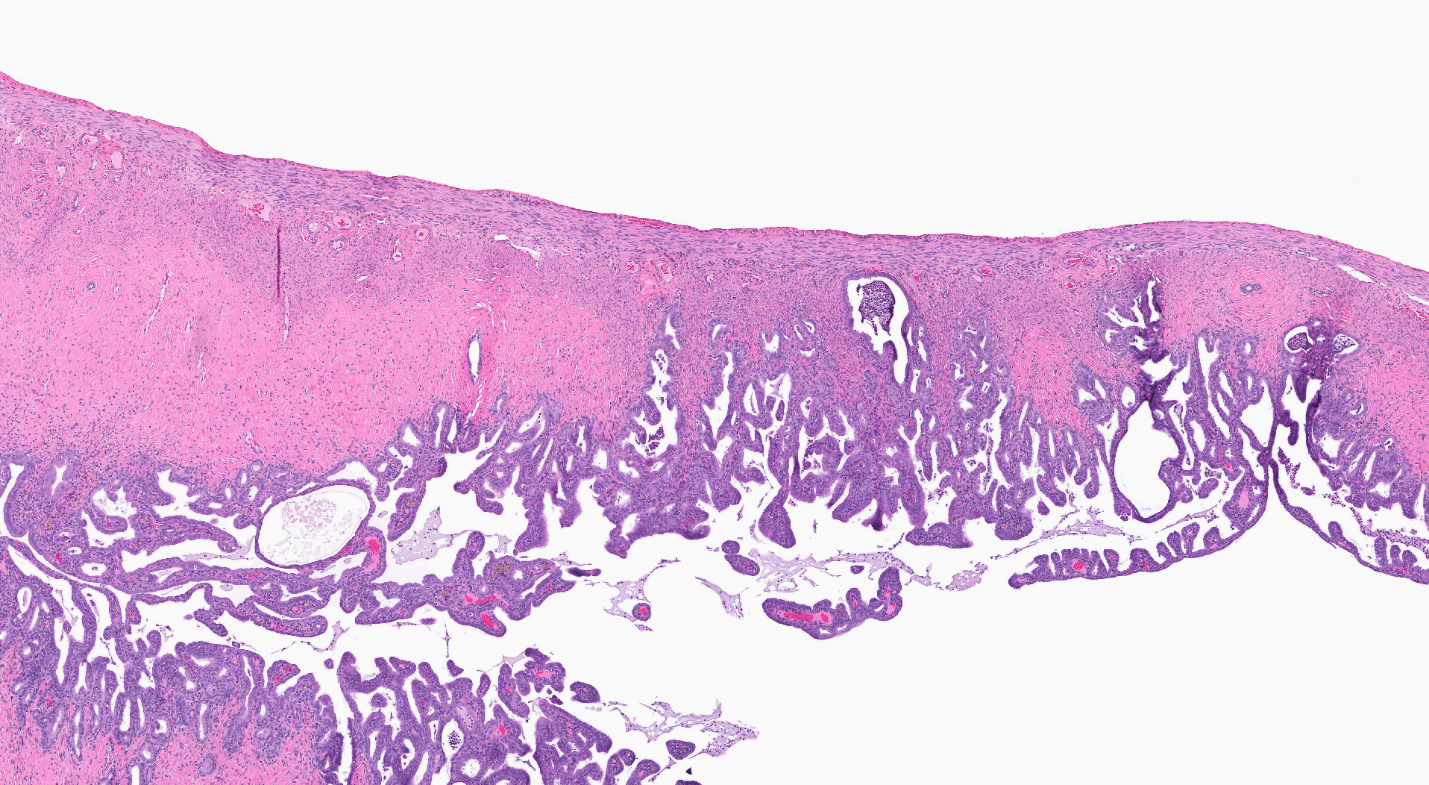

The effect of chronic TCPP exposure was evaluated in rats, beginning in utero and through adulthood, following feed administration at target concentrations of 0, 2,500, 5,000, 10,000, or 20,000 ppm TCPP. TCPP exposure to dams had no toxicologically relevant effects on maternal measurements during gestation or lactation with the exception of a slightly lower mean body weight and feed consumption in the 20,000 ppm group over this perinatal period. An exposure concentration-related decrease in mean body weight relative to control animals was observed in male and female offspring in the 20,000 ppm TCPP group during lactation. At the end of the 2-year study, mean body weights of males and females in the 20,000 ppm group were 8% and 17% lower, respectively, than those of the control groups. Histopathological evaluations identified a positive trend for incidences of hepatocellular adenoma or carcinoma (combined) in male rats. Accompanying significant nonneoplastic lesions included hyperplasia of the bile duct and an increase in basophilic, eosinophilic, mixed-cell foci, and pigment in the liver of males exposed to 20,000 ppm TCPP. A nonsignificant increase in the incidence of hepatocellular adenomas was observed in females exposed to 2,500, 10,000, and 20,000 ppm TCPP, and a spectrum of nonneoplastic lesions, similar to those in male rats, was observed. Histopathological evaluations also identified a positive trend for incidences of uterine adenoma or adenocarcinoma (combined) in female rats, although this was not significant at any exposure concentration.